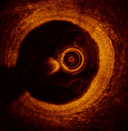

Coronarographie et imagerie invasive

Pr Jean-Guillaume Dillinger

CHU Lariboisière, AP-HP